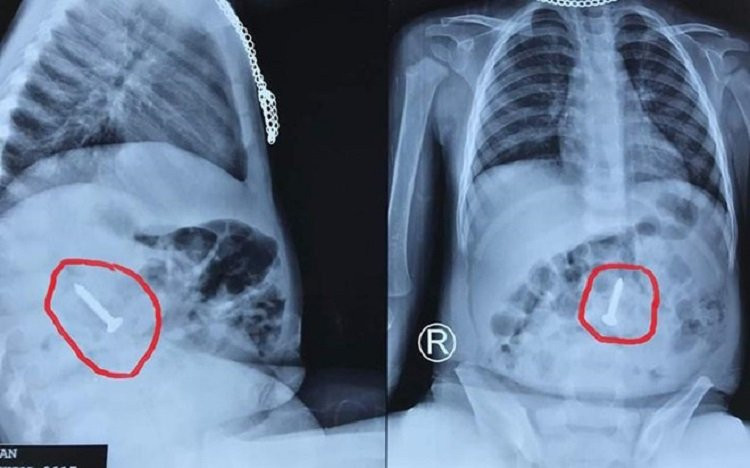

Theo thông tin từ Bệnh viện Hữu nghị Đa khoa Nghệ An, các bác sĩ vừa gắp thành công dị vật là chiếc đinh vít sắc nhọn dài đến 3,5 cm từ tá tràng của bệnh nhi ra ngoài an toàn.

Đinh vít sắt dài 3,5 cm trong bụng em bé 20 tháng tuổi

Bé N.H.H. (20 tháng tuổi) nhập viện ngày 14/6, bác sĩ chẩn đoán bệnh nhi nuốt phải dị vật kim khí.

Kết quả nội soi cho thấy tại đoạn cuối tá tràng của bé có hình ảnh dị vật kim loại một đầu sắc nhọn, có thể đâm thủng ruột, dạ dày của bé, gây nguy hiểm đến tính mạng.

Ngay lập tức, các bác sĩ nội soi gắp đinh vít sắt ra ngoài an toàn bằng phương pháp thòng lọng.